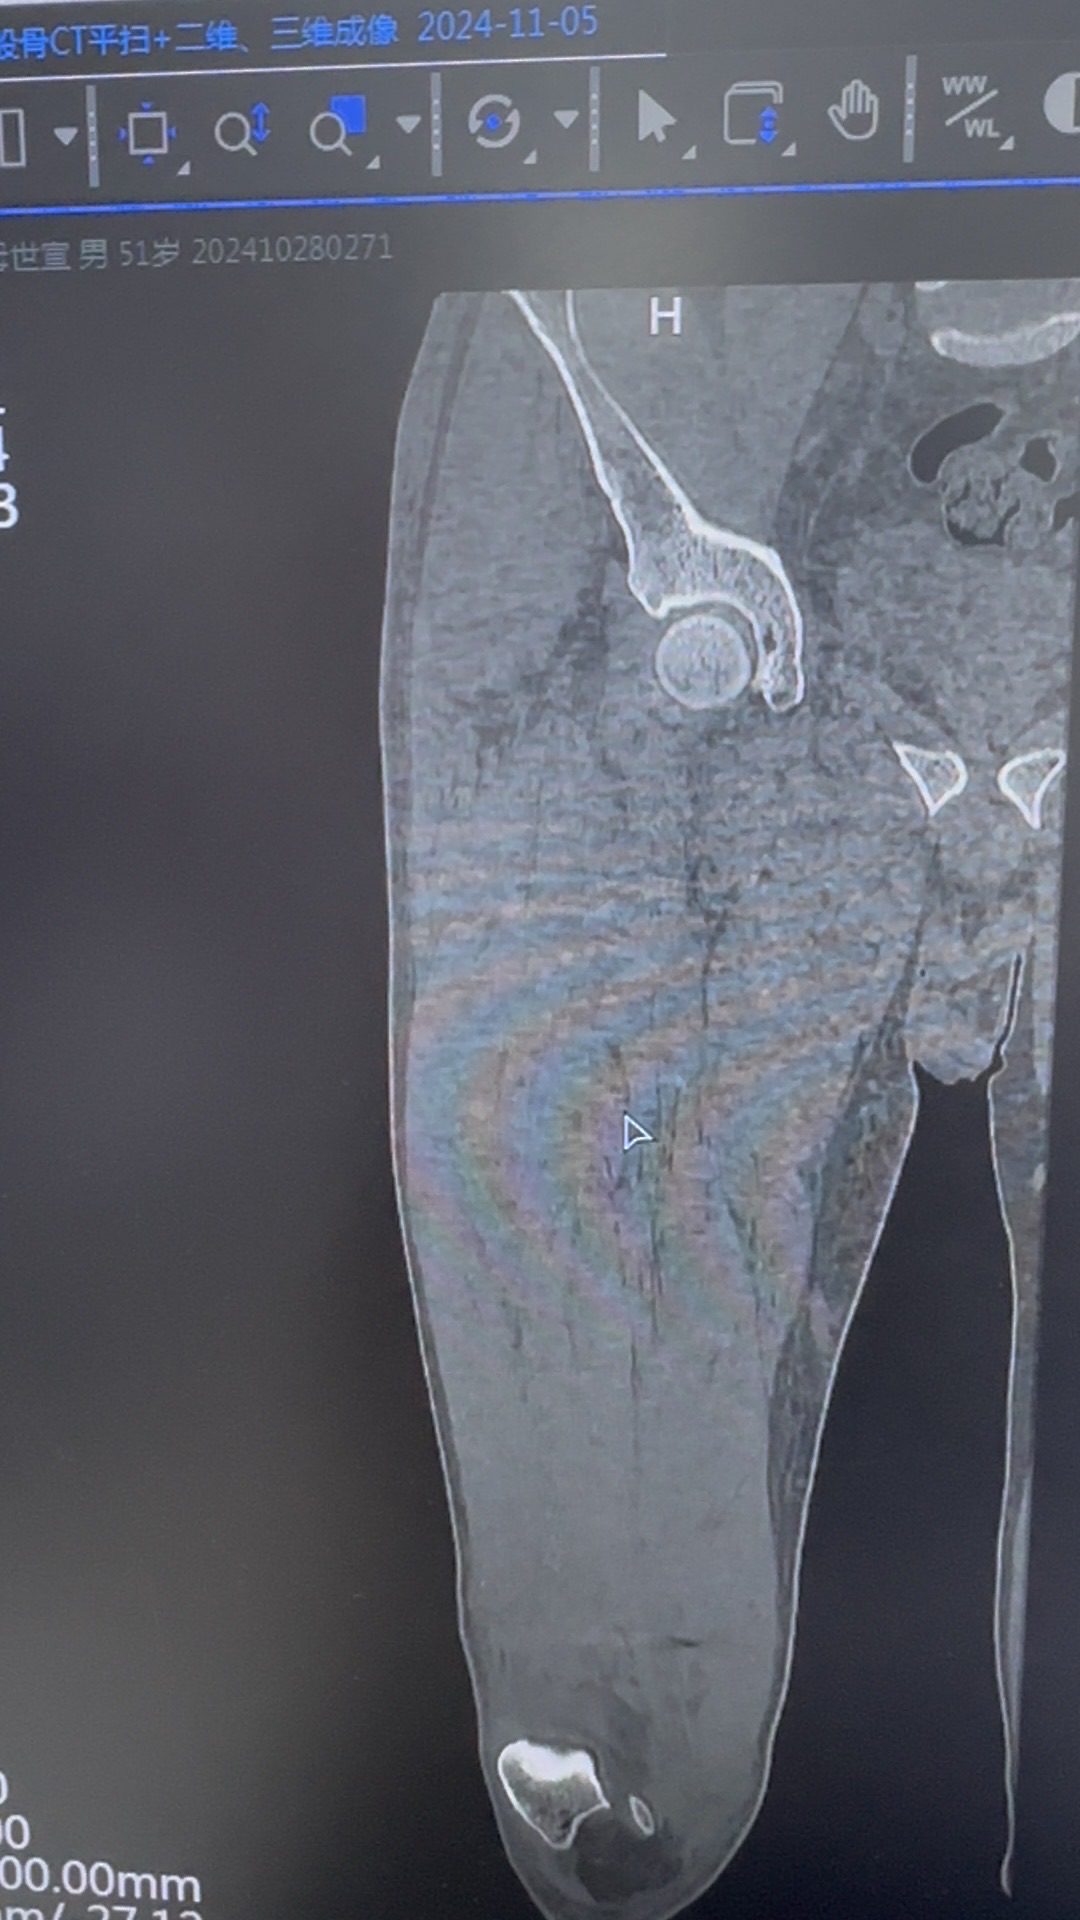

【患者信息】:51岁,男性,高处坠落伤

【主诉】:摔倒致右髋部肿痛活动受限2天入院

【临床诊断】:粗隆下骨折,seinsheimer Ⅴ型

【治疗经过及结果】:切开复位内固定

螺旋刀片位置不佳的原因在哪?复位欠佳?髋内翻?内固定开口偏后?主钉深度不够?